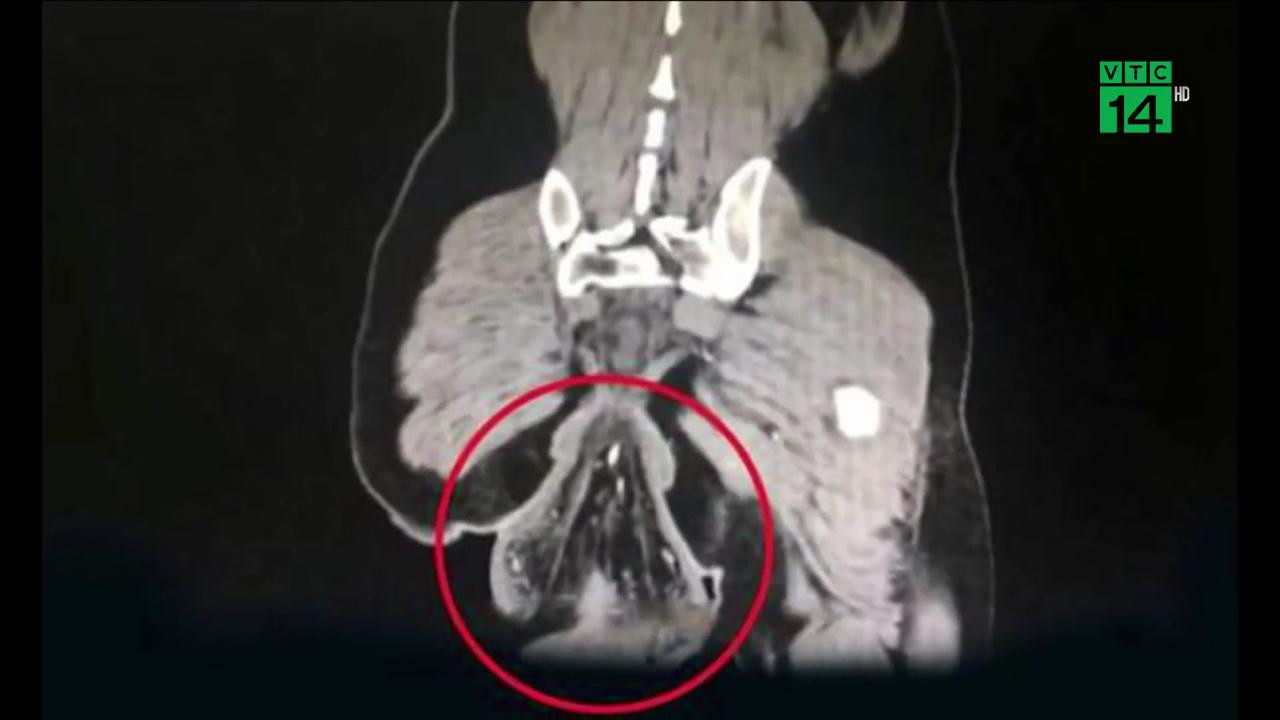

Người đàn ông Trung Quốc được đưa tới bệnh viện vào lúc nửa đêm trong tình trạng sa trực tràng nghiêm trọng sau khi chơi game trên điện thoại liên tục 30 phút khi đi vệ sinh.

- sa trực tràng

- rơi trực tràng ra ngoài